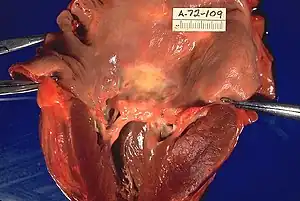

Cause

Almost all cases of mitral stenosis are due to disease in the heart secondary to rheumatic fever and the consequent rheumatic heart disease.[3][5] Uncommon causes of mitral stenosis are calcification[6][7] of the mitral valve leaflets, and as a form of congenital heart disease. However, there are primary causes of mitral stenosis that emanate from a cleft mitral valve. It is the most common valvular heart disease in pregnancy.[8]

The normal area of the mitral valve orifice is about 4 to 6 cm2. In normal cardiac physiology, the mitral valve opens during left ventricular diastole, to allow blood to flow from the left atrium to the left ventricle. A normal mitral valve will not impede the flow of blood from the left atrium to the left ventricle during (ventricular) diastole, and the pressures in the left atrium and the left ventricle during ventricular diastole will be equal. The result is that the left ventricle gets filled with blood during early ventricular diastole, with only a small portion of extra blood contributed by contraction of the left atrium (the "atrial kick") during late ventricular diastole.